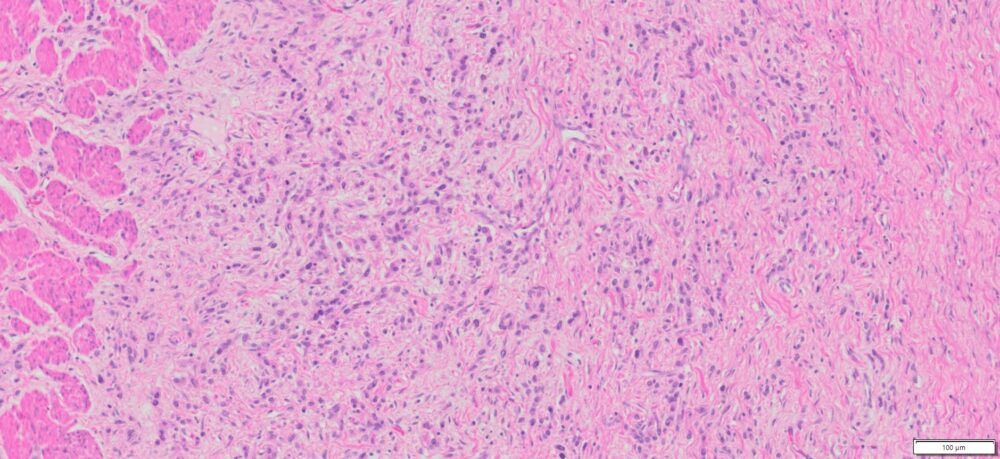

| Organ& Tissue | Pathology Diagnosis | Gender/Age | % Tumor Area | Grade | TMN Stage | Biomarkers |

| Human stomach | Poorly differentiated adenocarcinoma of the stomach | Male/52 | 10% | III | T3N3bMo |